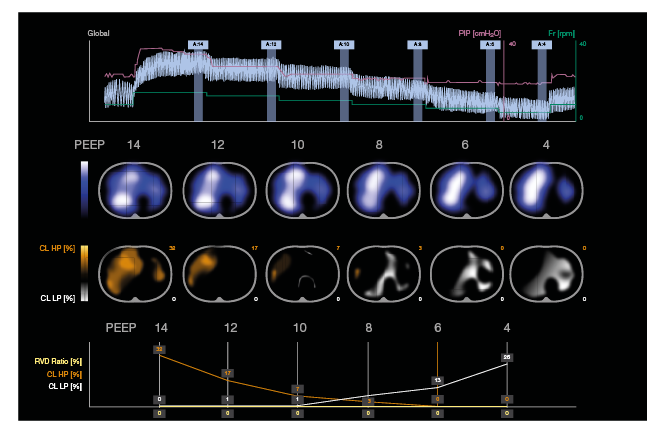

Esta semana nuestro compañero Ignacio Carnerero presenta los resultados clínicos de los primeros pacientes #ecmo. Efectividad y Seguridad tras la implementación de un protocolo multidisciplinar: Cirugía Cardiaca, Perfusionistas, UCI y Enfermería. #CONGRESOSEMICYUC2023

Esta semana nuestro compañero Ignacio Carnerero presenta los resultados clínicos de los primeros pacientes #ecmo. Efectividad y Seguridad tras la implementación de un protocolo multidisciplinar: Cirugía Cardiaca, Perfusionistas, UCI y Enfermería.